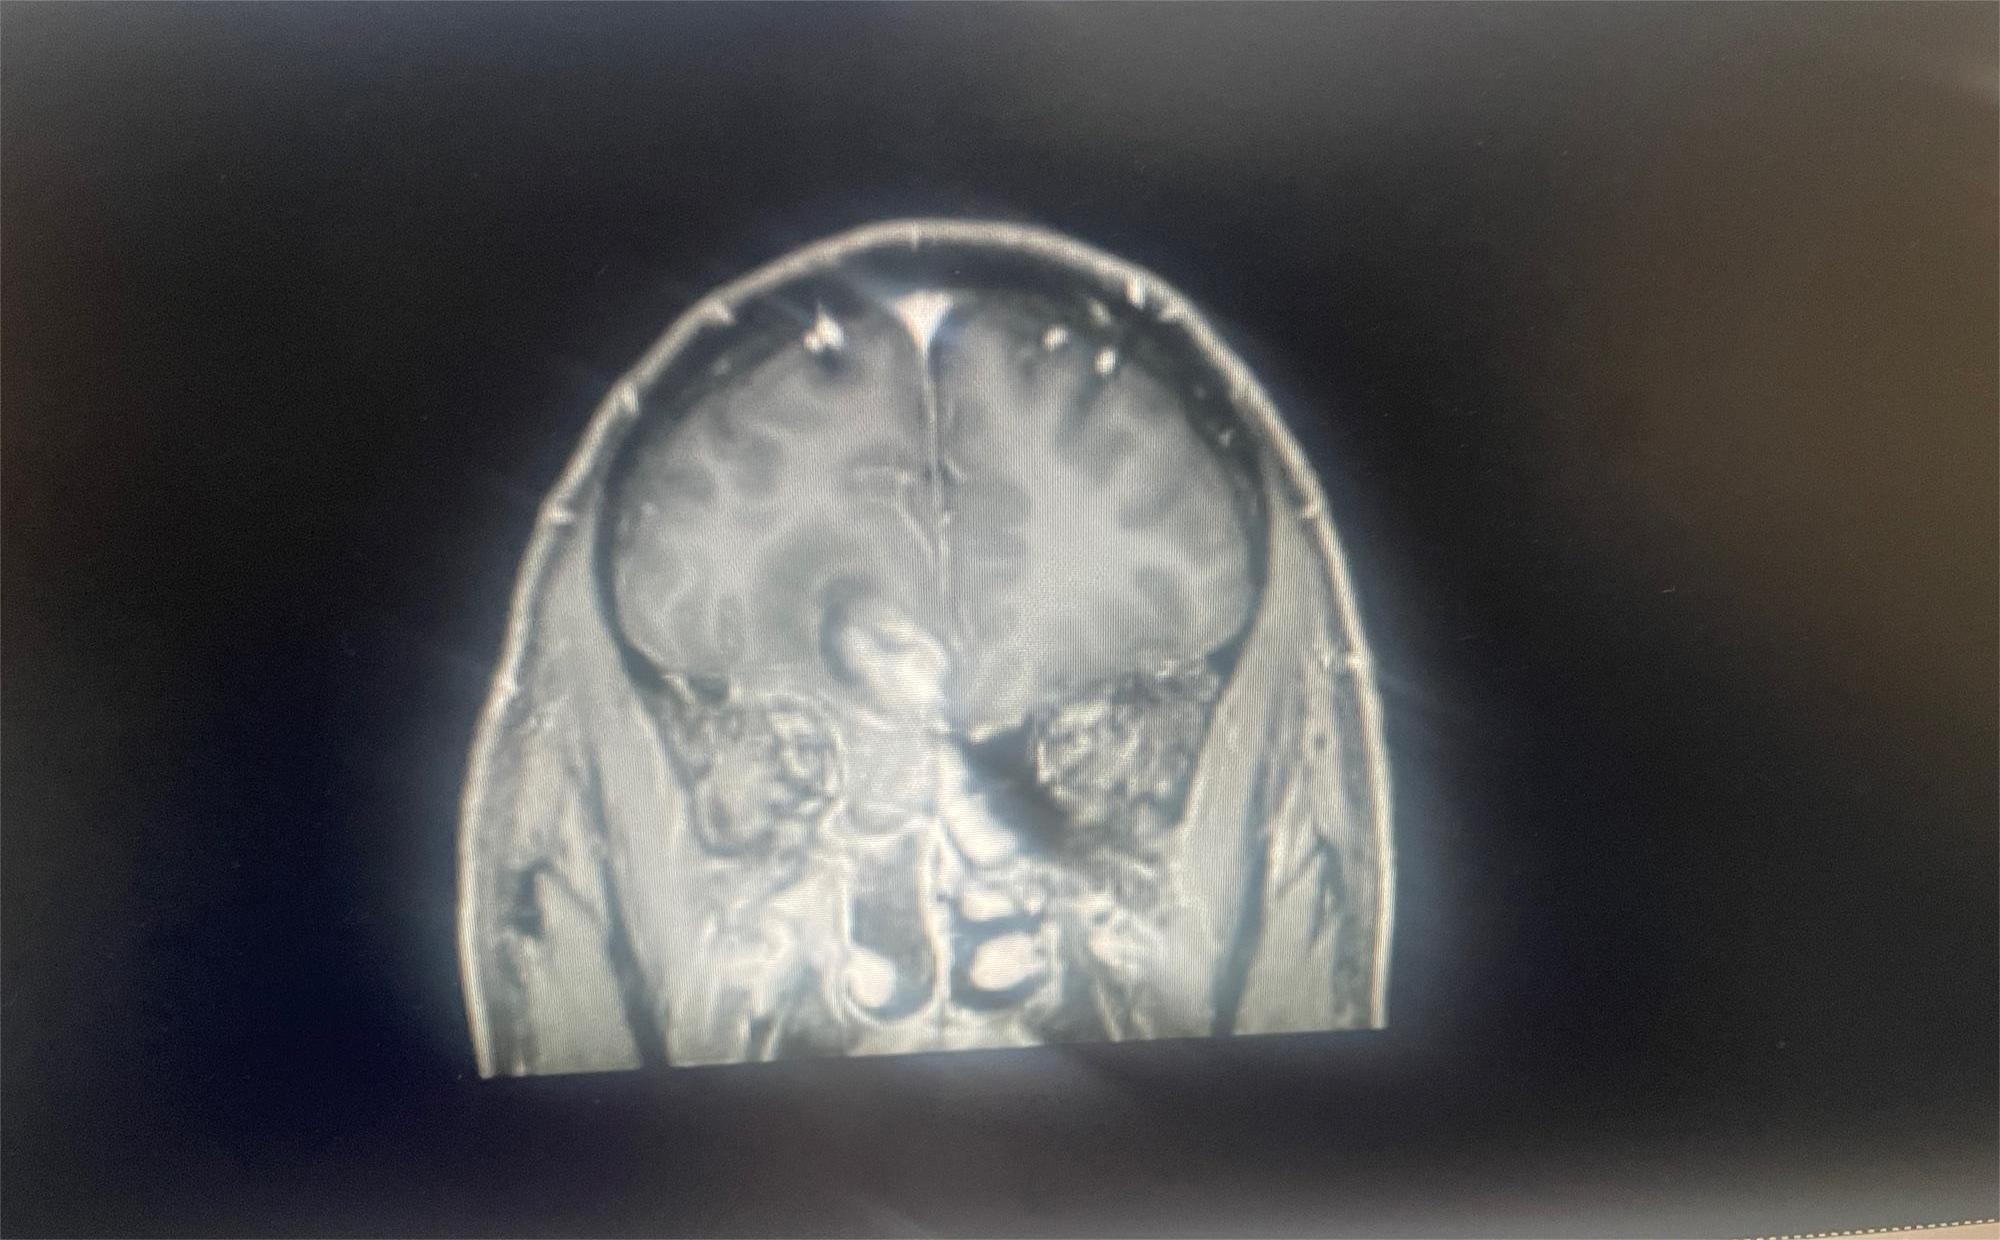

共1张

脑部肿瘤求助